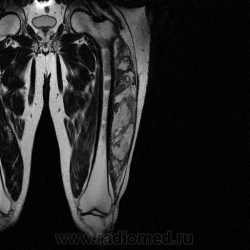

Ну вот аксиальные срезы, где то затерял =(

С учетом вашего опыта, мне кажется Вам и без дословной интерпретации МР-протокола будет все понятно.

Мой коллега в заключении указал о вероятней всего рабдолейомиосаркоме, если я ошибся то чуть позже поправлюсь.

Я тоже пока что в этом деле лось, но думаю дело поправимое, на днях улетаю С-Петербуг в МАПО(цикл КТ и МРТ), ну да ладно, что косается пациента то он ещё в 2007 году обращался по месту жительства к травматологу по поводу ушиба бедра с формированием гематомы, была назначена местная рассасывающая терапия, до 2009г. видимо ждали пока рассасется в декабре обратился к хирургу по поводу посинения и увеличения в объёме задней поверхности бедра, назначен гепарин в феврале был вскрыт абсцесс в этом месте, далее только в марте сподхватились по УЗИ-мягких тканей признаки образования, ну и открытая ножевая биопсия: Описание изменений, выявленных при микроскопическом исследовании: в материале фрагменты опухоли, представленной пучками вытянутых клеток с полиморфными гиперхромными, местами уродливыми ядрами. Определяется значительное количество митозов, встречаются поля некроза опухоли. При иммуногистохимическом исследовании опухолевые клетки экспрессируют виментин, отсутствует реакция на десмин, гладко-мышечный актин, S100. Патоморфологическое заключение: саркома мягких тканей, боее вероятно фибросаркома.